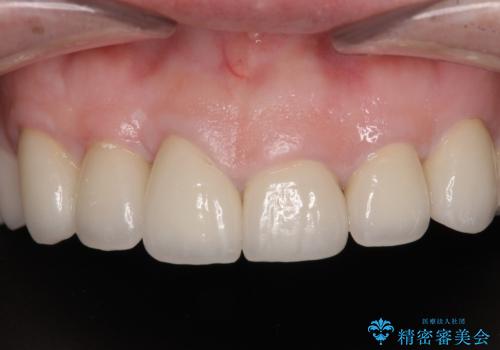

上顎前歯は樹脂を外し、下顎前歯の隙間はそれぞれの歯を大きくするように補綴治療を行うことで隙間を埋めることとしました。

口を開けたときに見える範囲をオールセラミッククラウンとし、とても自然な口元に仕上げることができました。